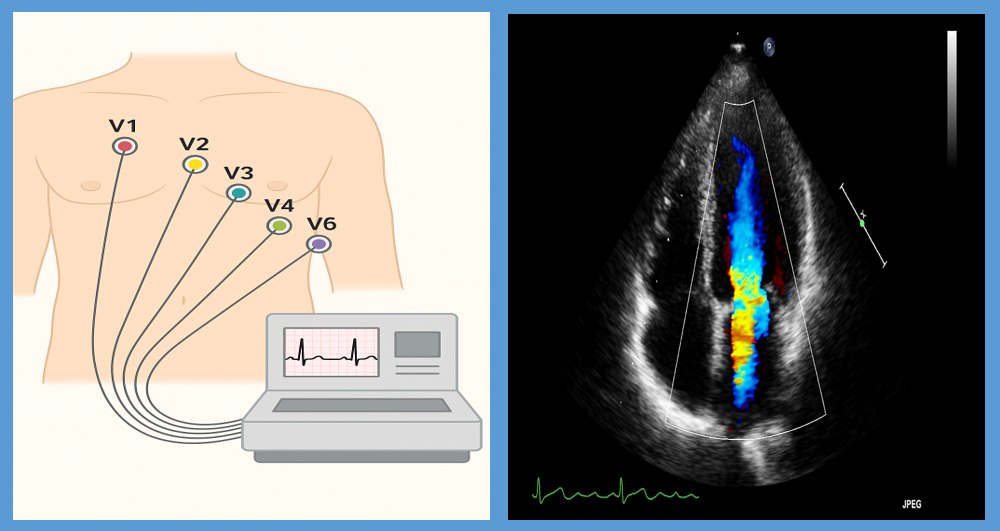

① 심전도 검사 (ECG)

심장의 전기신호를 확인하는 기본 검사입니다.

가만히 있을 때는 정상이라도, 운동 중 심전도 변화가 생기면 협심증을 의심할 수 있어요.

→ 운동부하 심전도라고 해서 러닝머신에서 걷거나 뛰며 검사하는 경우도 많아요.

② 심장 초음파

초음파로 심장의 구조와 움직임을 살펴봐요.

심장이 혈액을 잘 내보내고 있는지, 벽이 고르게 움직이는지 등을 확인해

간접적으로 혈류 장애를 판단할 수 있어요.